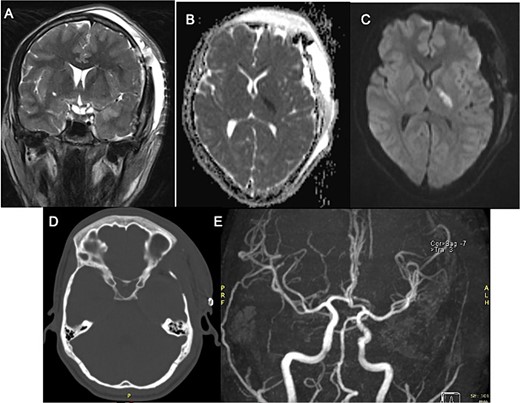

Postoperatively, the patient developed progressive right-sided hemiparesis and altered consciousness progressing to stupor, attributed to vasospasm of the left anterior choroidal artery. Evidence of arterial narrowing was observed in the postoperative angiography with MR (Fig. 2E). No endovascular chemical angioplasty was performed due to ischemic findings on FLAIR sequence. Following rehabilitation, the patient was discharged home with improved strength (|$ \frac{4}{5} $|).

Postoperative MRI with left third cranial nerve decompression in T2-weighted sequence (A) and a high DWI signal and low ADC signal in the posterior limb of left internal capsule (B, C) with no occlusion in angiogram MRI demonstrating ischemic event (E) Head CT Scan (D) without compressive lesion.